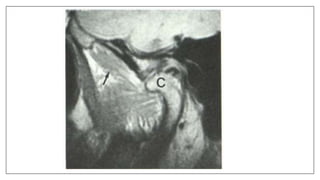

Normal anatomy

Pathologies

Stuck disk Phenomenon inTMJ

• A stuck disc refers to aTMJ disc which does not translate anteriorly out of

the mandibular fossa onto the articular eminence, but rather remains (thus

"stuck") in the fossa. It is a form ofTMJ dysfunction and is typically

associated with restricted range of motion.

• Its due to fibrous adhesions